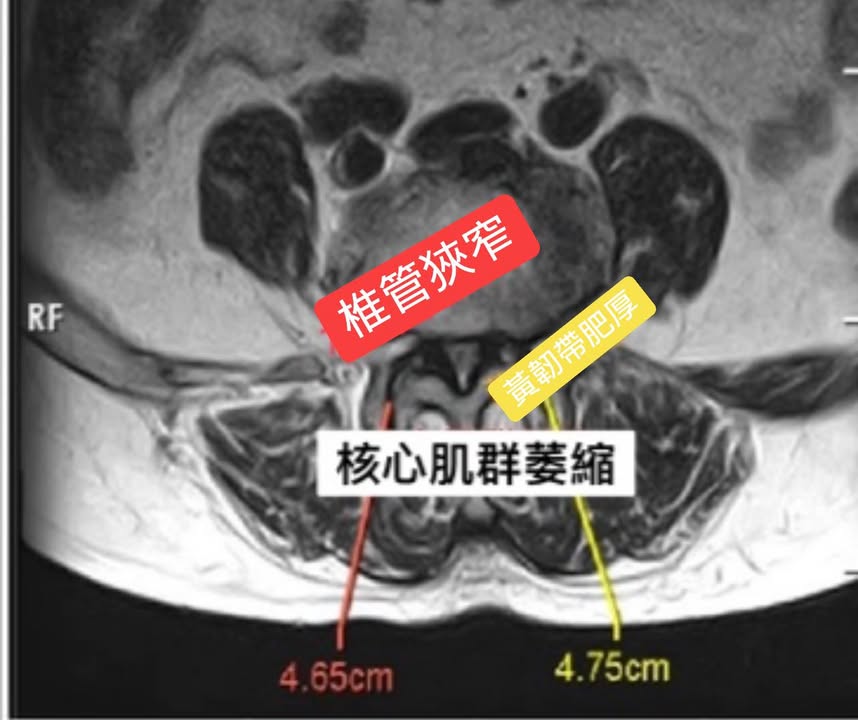

🎦這個案例印象深刻,83歲的曹阿姨原本預定12/30開刀,阿姨的女兒經過友人介紹趕快在開刀前五天帶媽媽北上,完整的諮詢之後,我判斷阿姨無法走路的原因是因為核心肌肉量嚴重不足,雖然腰椎滑脫與椎管狹窄也是本病的主因,但如果要不想開大刀,勢必要好好訓練肌肉

4️⃣黃韌帶肥厚 – 背部韌帶退化時會變得僵硬及厚實。腰椎管狹窄症的元凶通常都是椎管內的黃韌帶。黃韌帶變厚可壓著神經,而僵硬的韌帶則妨礙脊柱的正常活動。

一般來說,單純的脊椎狹窄壓迫神經,是因為長期彎腰導致脊椎兩旁的黃韌帶(ligamentum flavum)肥厚增生進而壓迫到神經,只要未伴隨脊柱嚴重滑脫,通常只要將黃韌帶減壓,讓神經不再受到壓迫即可,之後訓練患者核心肌群,讓筋膜當作自己的最強骨架,原則上開刀是最後最後要選的路。

💢註:黃韌帶是脊柱椎管內用來維持脊柱穩定性的一個韌帶組織結構,它屬於脊柱後柱的支持結構之一。長期的坐姿或彎腰工作容易導致肥厚增生,常引起椎管的狹窄,嚴重者會出現腰痛和下肢的疼痛和麻木。